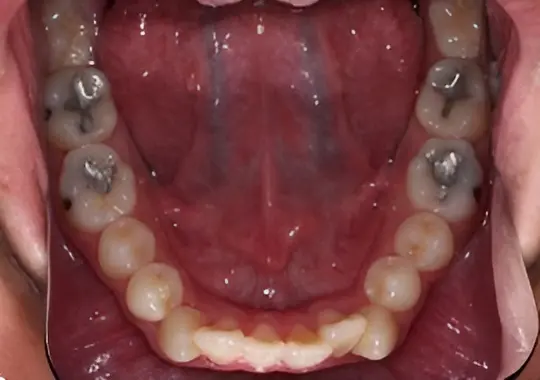

Before

After